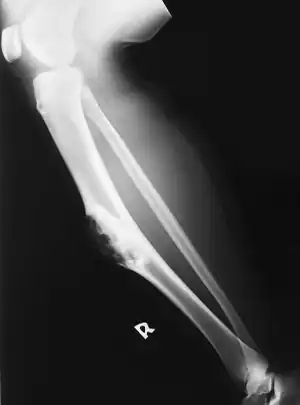

Osteofibrous dysplasia of tibia (lower leg)

Osteofibrous dysplasia is a noncancerous bone tumor.[1] It most often affects the large long bone of the lower leg in young children.[2][3]

It is considered a fibrovascular defect. Campanacci described this condition in two leg bones, the tibia and fibula,[4] and coined the term.

Osteofibrous dysplasia most often presents as a localized firm painless swelling of the large long bone of the lower leg in young children.[2] The leg may appear bent and it is possible that a break in the bone can occur.[2][5]

Diagnosis is by x-ray.[2]

It is rare, particularly over the age of 15 years.[2] The frequency of occurrence is not known precisely.[2] The tibia accounts for around 90% of cases.[2][6] The long bones of the arm are unlikely to be affected.[2] Boys and girls appear affected equally.[2]